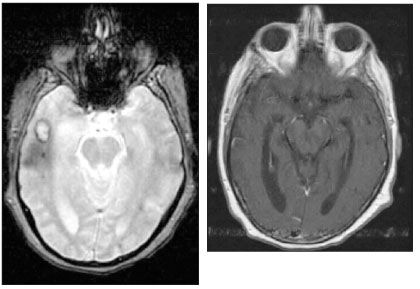

Follow-up brain MRI performed 2 weeks later while the patient was receiving therapy for both Toxoplasma and MAI infections demonstrated a decrease in the size of the lesions and surrounding edema (Figure 6); a brain biopsy was therefore not pursued. Within 2 months, serial MRI scans showed complete resolution of the brain lesions except for residual hemorrhagic changes (Figure 7), and the patient’s skin lesions had not recurred. Because the patient was being treated for an opportunistic infection and he had never taken his original antiretroviral regimen, the same regimen was finally started.

Figure 6.Axial gradient brain MRI scan demonstrating a decrease in the size of the lesion and surrounding edema after 2 weeks of therapy. Figure 7.Axial gadolinium brain MRI scan demonstrating resolution of lesion in the right temporal lobe 2 months after the patient started therapy.